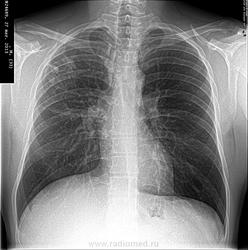

Добрый день.Мужчина 1980 года рожения.Диагноз:Инфильтративный туберкулёз правого лёгкого в фазе распада.Лечение длится 6 месяцев.Я высылаю все снимки ,которые были сделанны во время лечения.меня интересуют вопросы:

1)Какова динамика?

2)Надо ли продолжать лечение ,после сделанного последнего снимка(27/03/2013)?

Динамика положительна,но нужны томограммы,хотя бы линейные.Вопрос о прдолжении лечения решает лечащий врач,обычно на таком сроке лечение продолжают.

каковы результаты посевов? Устойчивость? Желательны томограммы. На вскидку-уплотнение и организация, +динамика. Туберкулез такая штука,медлительная)))

Томограмму делали в начале лечения,после врач не назначал.Устойчивости нет.Посев мокроты в начале лечения БК+-,после 2-х месяце лечения БК-.Больной чувствовал себя хорошо,туберкулёз выявлен при профилактическом осмотре(случайно).Лечение принимал амбулаторно.